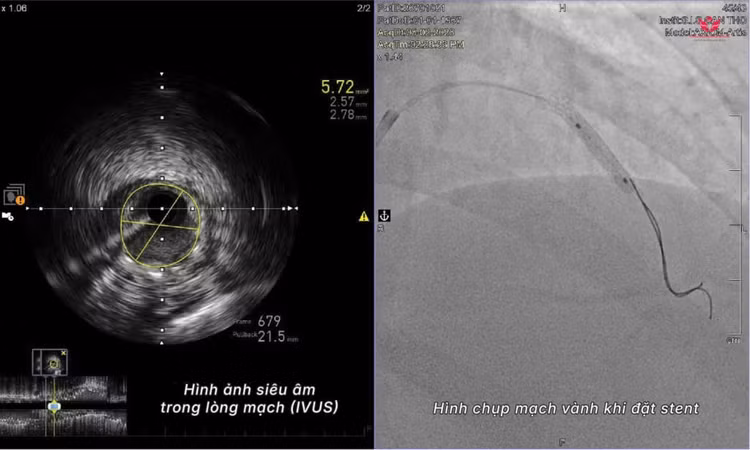

Hình ảnh chụp mạch vành trước và sau can thiệp - Ảnh BVCC

Bác sĩ Chỉnh cho biết: Chúng tôi đã có dữ liệu hình ảnh CT mạch vành trước đó để định hướng các mốc giải phẫu. Trong quá trình can thiệp, thay vì dùng thuốc cản quang, ê-kíp sử dụng siêu âm trong lòng mạch (IVUS) để quan sát trực tiếp bên trong động mạch và tiến hành đặt stent tái thông thành công.

Bác sĩ CKI Nguyễn Đức Chỉnh chia sẻ, để thực hiện can thiệp mạch vành không sử dụng thuốc cản quang, các đơn vị y tế cần đáp ứng hai điều kiện: Bác sĩ cần nắm rõ giải phẫu mạch vành của bệnh nhân từ trước thông qua các dữ liệu hình ảnh, đồng thời đơn vị phải có các thiết bị hình ảnh nội mạch chuyên sâu như siêu âm trong lòng mạch (IVUS) để quan sát trực tiếp lòng và thành động mạch.